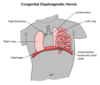

Malformation of the diaphragm allowing herniation of abdominal contents into the thoracic cavity

Congenital Diaphragmatic Hernia

Results in Prevention of prenatal lung development/lung hypoplasia

Which side of the diaghragm is mostly affected by Congenital Diaphragmatic Hernia? Why?

Left side

90% occur on left side

Left side Foramen of Bochdalek closes later than right

Clinical features of Congenital Diaphragmatic Hernia

Scaphoid abdomen

Breath sounds absent on involved side

Lung hypoplasia = respiratory distress syndrome